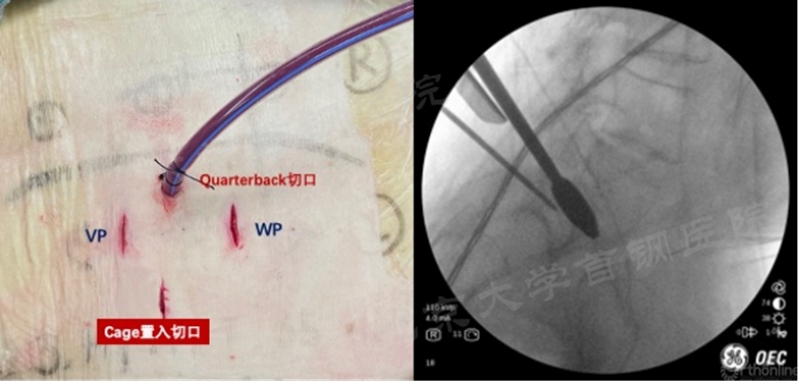

4. 在常规UBE-LIF中作为放置硬膜牵开装置的通道,有时将其称为Quarterback-K切口。我中心现常规通过此切口放置克氏针进行硬膜牵拉,显著提高处理椎间隙、纤维环缝合过程中的安全性和效率(图4);

图4 我中心使用克氏针经Quarterback切口对硬膜进行牵拉(图片来源我中心,引用转发需注明出处)